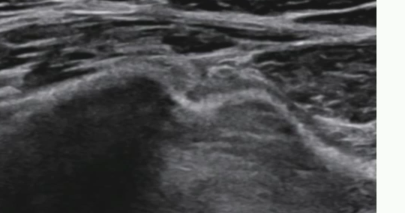

Test du valsalva

Hernie fémorale